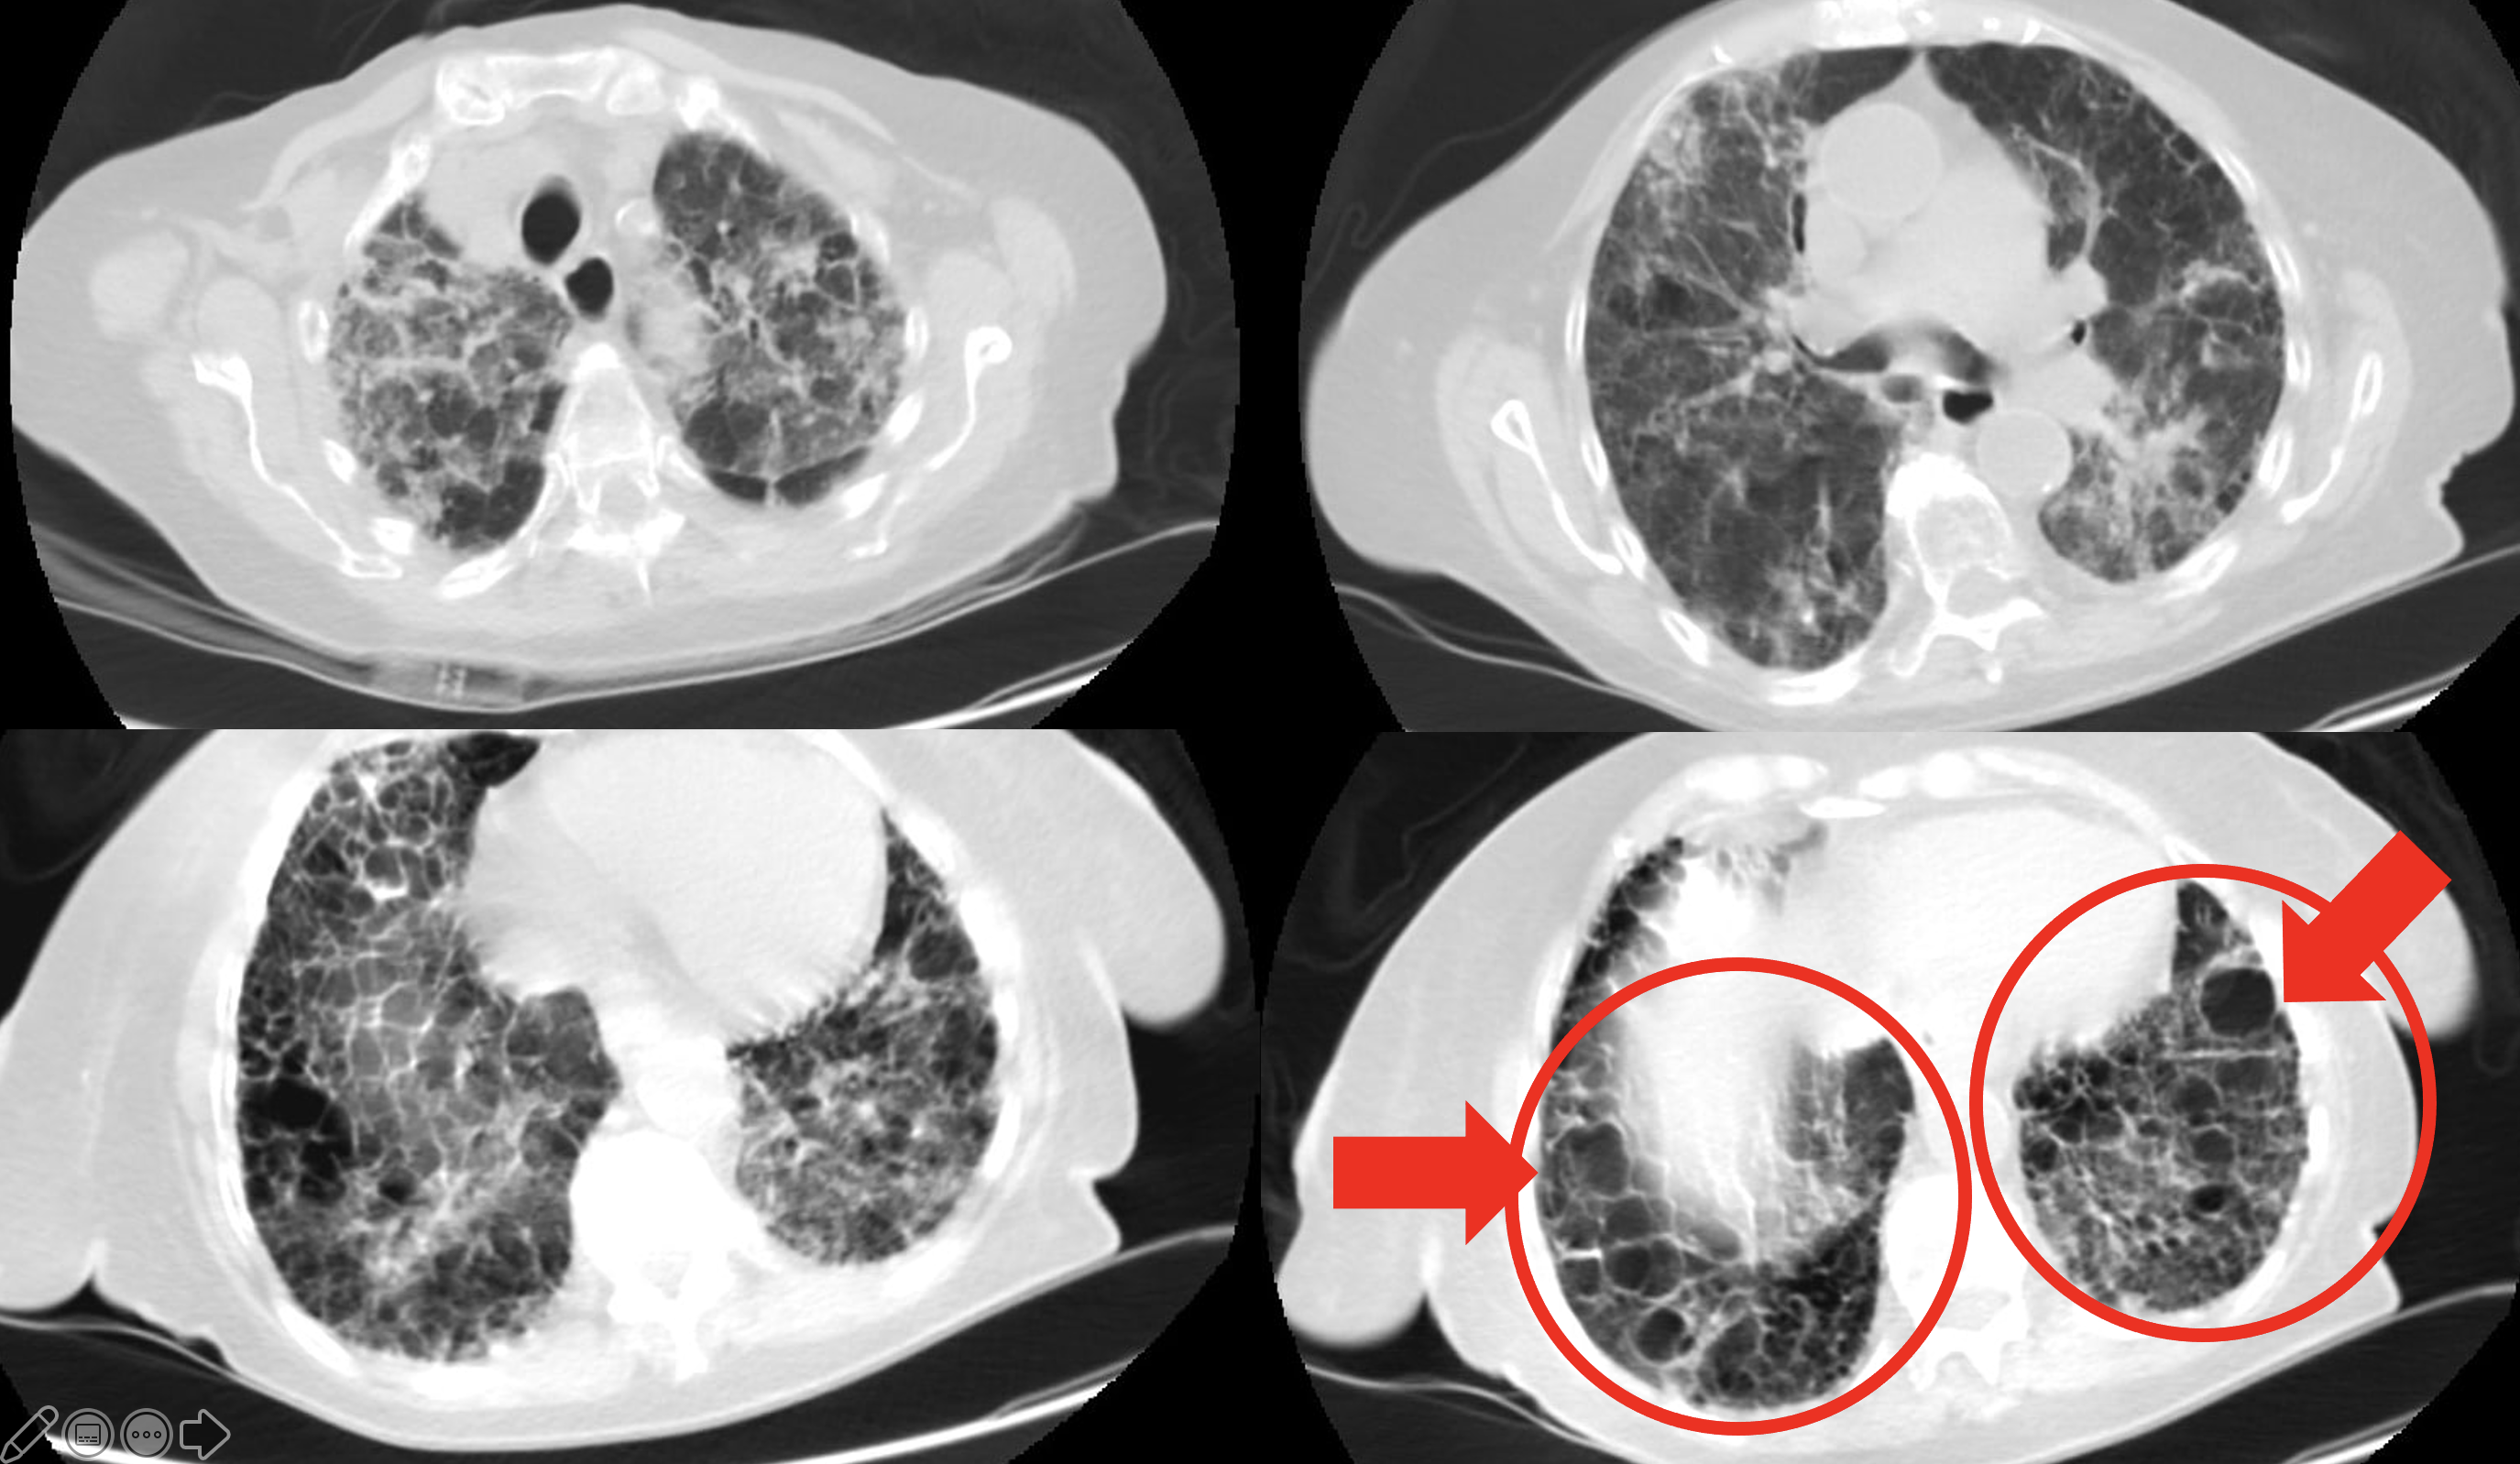

Булл обоих легких